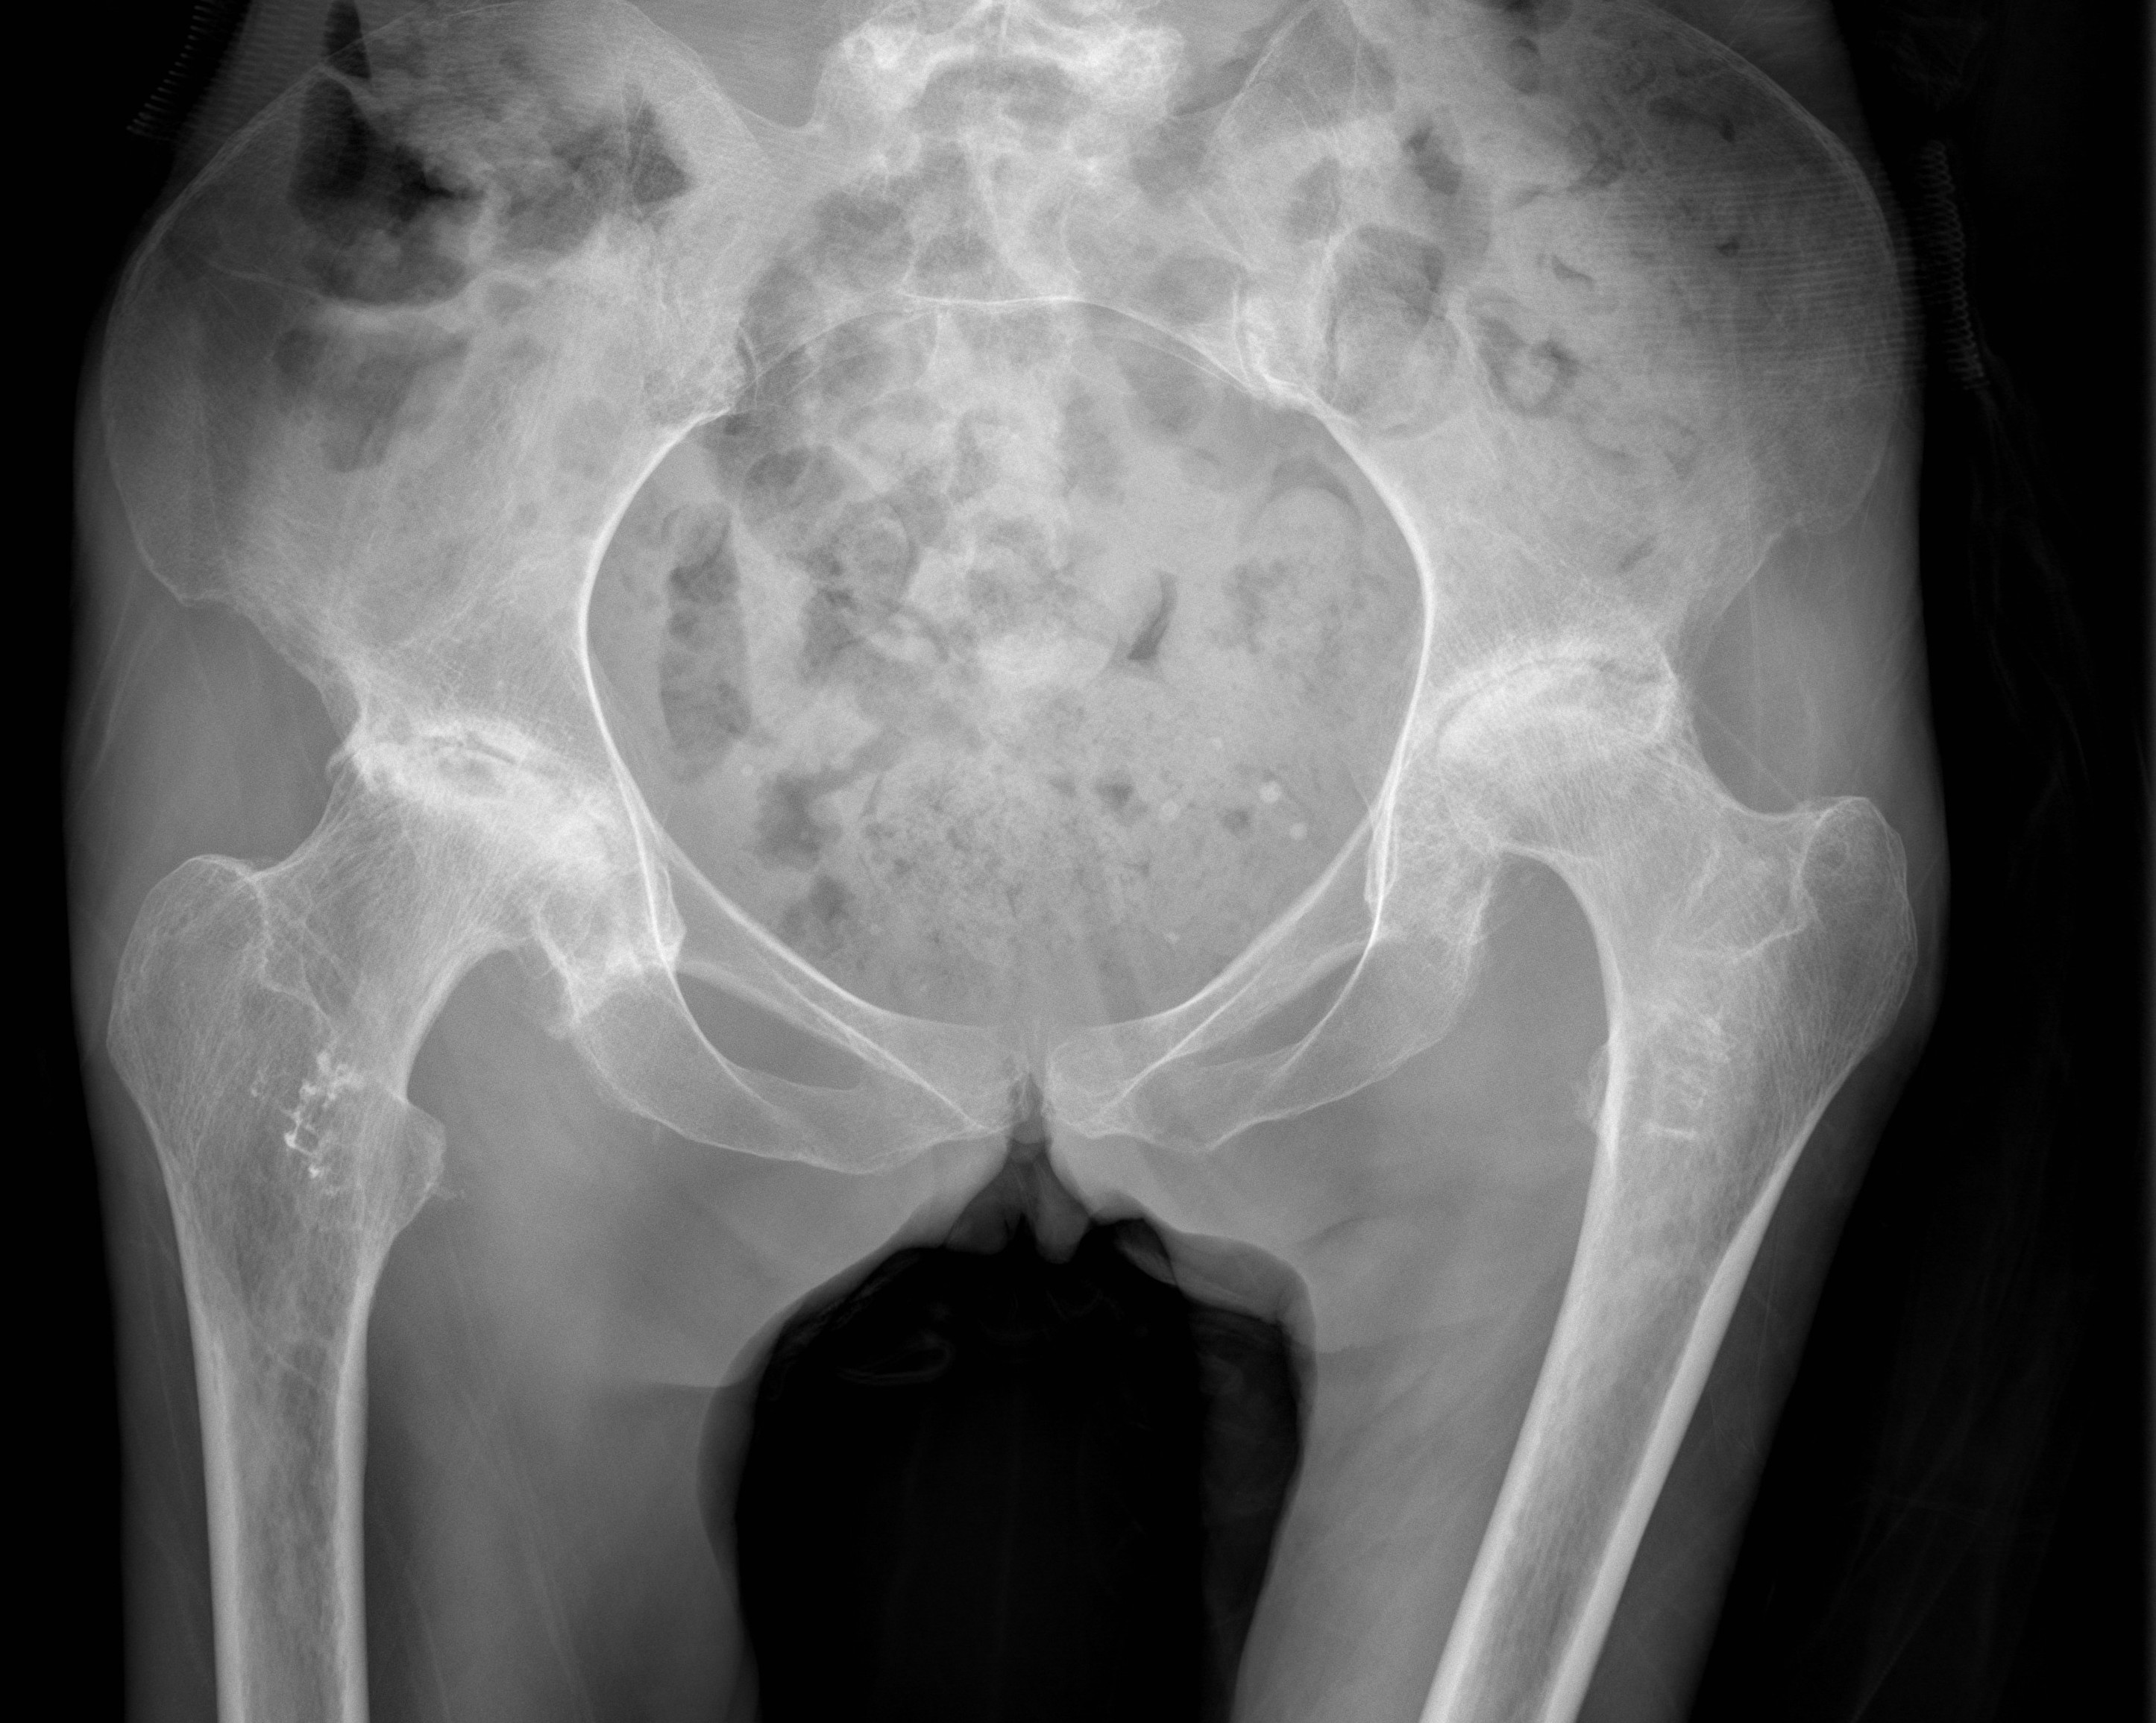

- sickling occurs with relative hypoxia

- trapped in blood vessels

- necrosis & pain